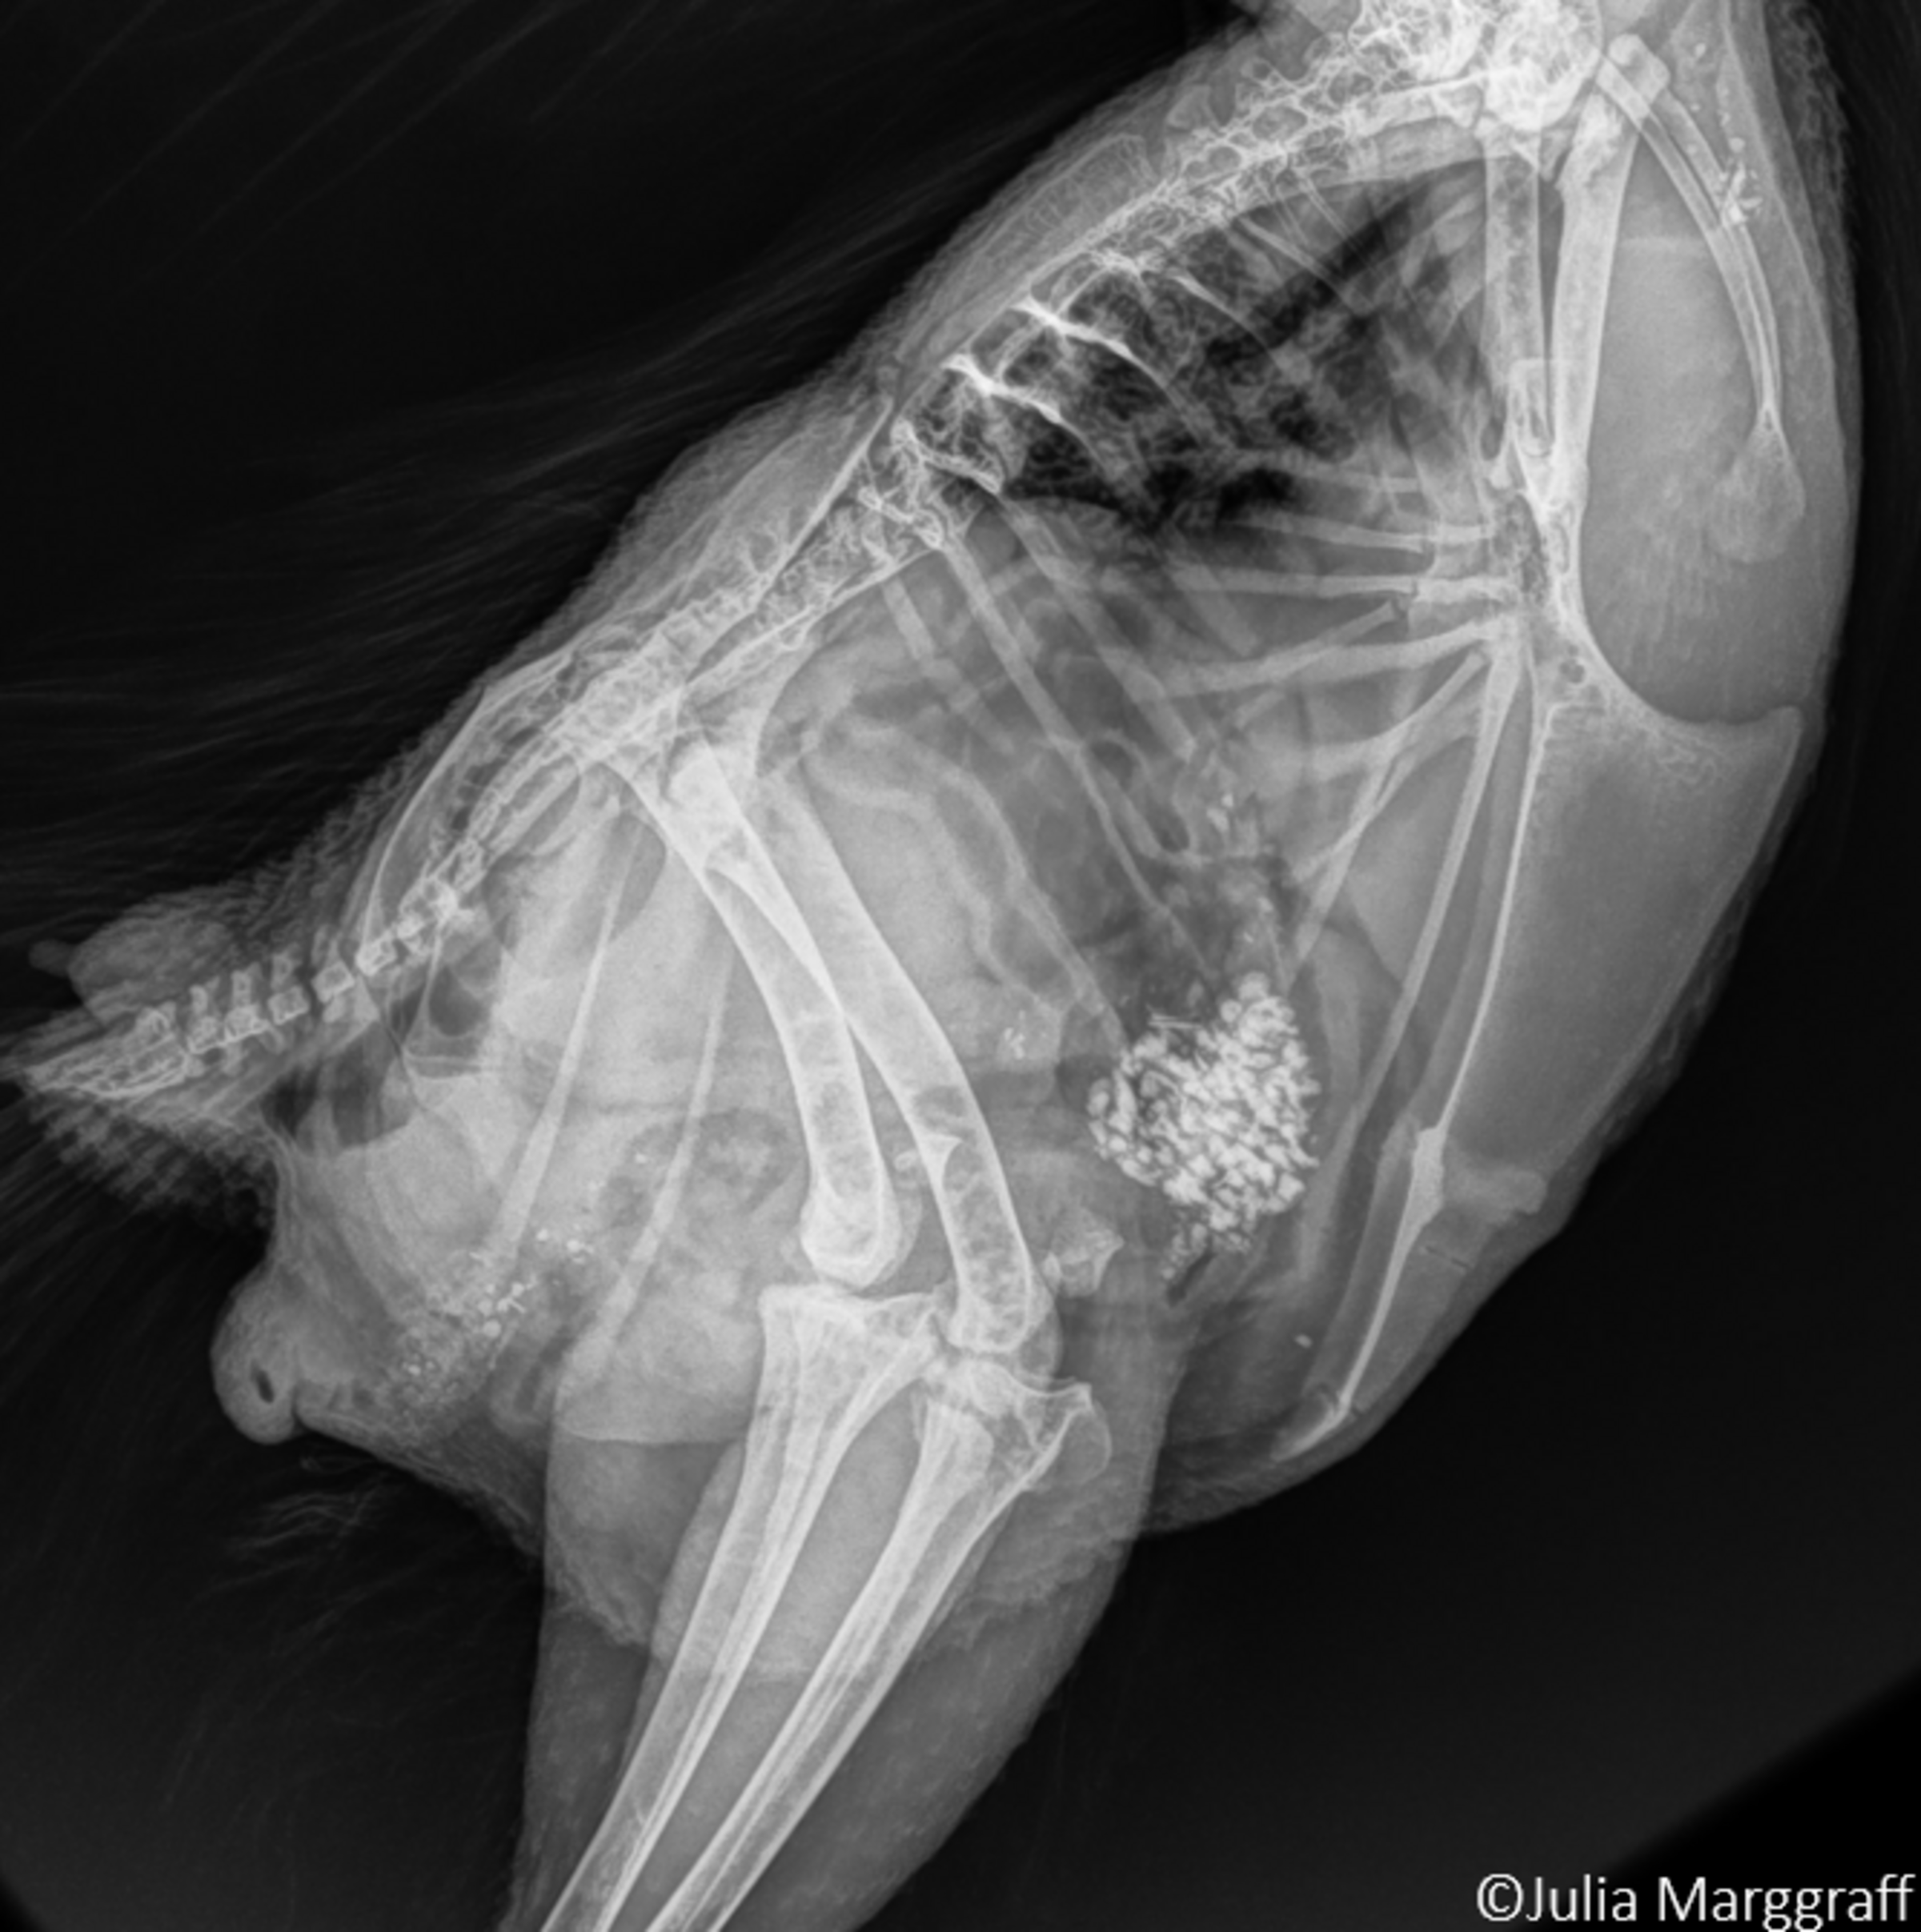

Bei Knochenbrüchen wird zwischen traumatisch bedingten und atraumatischen Frakturen unterschieden. Im Gegensatz zur traumatisch bedingten fehlt bei der atraumatischen Fraktur eine externe Krafteinwirkung als Ursache (z.B. Aufprallen auf eine harte Kante). Bei diesen Frakturen sind die Frakturenden am Knochen oft sehr dicht beisammen und die Knochenhaut bleibt intakt. Im Röntgenbild stellen sie sich als feine Haarrisse dar. Diese Frakturen treten meist bei älteren Hennen als Folge von Knochenermüdungen oder Osteoporose auf. Bei traumatisch bedingten Frakturen ist der Schweregrad abhängig von der Krafteinwirkung. Je schwerwiegender die Kollision im Haltungssystem oder je größer die Kraft, desto größer der Zerstörungsgrad am Knochen. Das Spektrum reicht dabei von kleinen abgebrochenen Knochenenden bis zu schweren Trümmer- oder Splitterfrakturen. Im Lauf der Haltungsperiode kann das Brustbein einer Legehenne mehrmals brechen. Beide beschriebenen Frakturformen können am selben Tier auftreten.

Da in den wenigsten Ställen Röntgengeräte zum Einsatz kommen, die für das Feststellen von Knochenbrüchen optimal wären, greift man auf die Methodik der Palpation zurück. Dabei tastet der Untersucher das Brustbein einzelner Hennen ab und erfühlt Abweichungen der „normalen“ Brustbeinform.